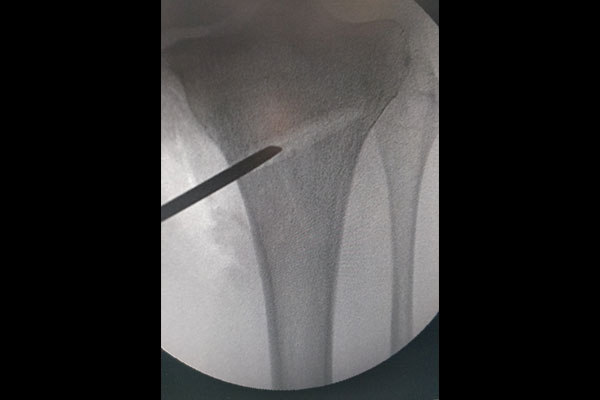

STEPS OF HTO